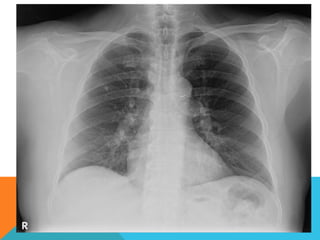

El estudio radiológico simple

evidencia una lesión nodular

menor del centímetro,

radiodensa, caracterizada como

granuloma cálcico.

En mi opinión el estudio de

TCAR fue realizado por ese

motivo y ello permito identificar

los hallazgos “floridos” que ya

se señalan y se muestran en las

imagen axiales ya

seleccionadas.

ABORDAJE TÉCNICO: Serealiza estudio con ventana mediastinal y de parénquima pulmonar con técnica de ALTA RESOLUCION, en inspiración y espiración, mediante  cortes axiales, desde ápices hasta bases pulmonares, con las siguientes observaciones En las partes blandas y las estructuras óseas dentro de los límites de la normalidad. Las regiones axilares libres. Ambos pulmones con neumatización conservada, con sobredistensión pulmonar, y áreas de atrapamiento aéreo, bilateral con cambios fibrosos cicatriciales apicales derechos. Se demuestran áreas de condensación en topografía predominantemente parenquimatosa pulmonar derecha, la mayor de ellas evidenciada hacia la base, acompañada de broncograma aéreo, la medición máxima al corte axial de 6.1 por 2.2 cm, en topografía del segmento posterior del lóbulo inferior, S10 así como también otra más se definen topografía de similares características en topografía del segmento medial del lóbulo medio, S5. En topografía parenquimatosa pulmonar izquierda imagen de similares características a las ya descritas en topografía del segmento lingular inferior, S4. No hay derrame ni áreas de engrosamiento pleurales. El patrón vascular es de características normales donde no se delimitan imágenes de lesiones aneurismáticas únicamente cambios por aortoesclerosis incipiente. El corazón de dimensiones conservada, de contornos regulares, sin desplazamientos; en la región hiliar derecha se define adenopatía de medición máxima corte axial de 1.6 por 1.4 cm.

El estudio radiológicosimple evidencia una lesión nodular menor del centímetro, radiodensa, caracterizada como granuloma cálcico. En mi opinión el estudio de TCAR fue realizado por ese motivo y ello permito identificar los hallazgos “floridos” que ya se señalan y se muestran en las imagen axiales ya seleccionadas.